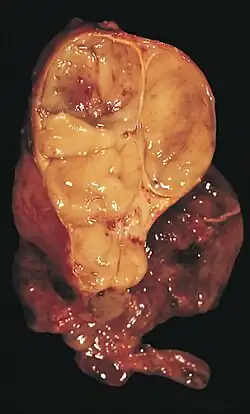

Les thymomes se présentent comme une masse bien définie du médiastin antérieur, proche du péricarde et dans un plan plus antérieur que les gros vaisseaux intrathoraciques (aorte ascendante et sa crosse, artère pulmonaire, veine cave supérieure). La masse peut être sphérique ou lobulée, mais présente un aspect homogène (plus rarement kystique) qui se réhausse après injection et peut contenir des calcifications[29].

L'irrégularité des contours de la tumeur, ainsi que la présence de calcifications, de nécrose ou d'hémorragie intratumorale sont des signes de mauvais pronostic corrélés à des tumeurs plus agressives[32].